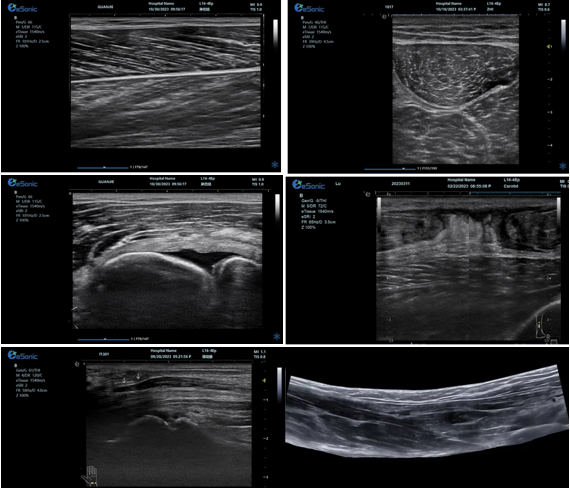

优异的图像质量

肌骨超声精确评估解决方案:

1、肌肉、肌腱、韧带专业评估

2、骨及软骨、滑膜及滑囊专业评估

3、神经病变及相关疾病临床应用

平面波超微细血流显像

彩色多普勒成像、3D壁滤波原理

血流敏感度明显提升,分辨率达微米级别

支持灰阶和微血流量同步测量、可测极低速血流的速度

多种模式,多数据定量评估。